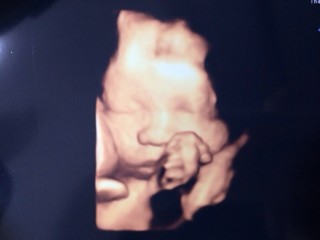

写真:30w0d:はるかさん:1600g

1600gの女の子、2週間前より400g大きくなってて標準だと言われました!パパに似てる気がするなぁ^^すくすく大きくなぁれ!